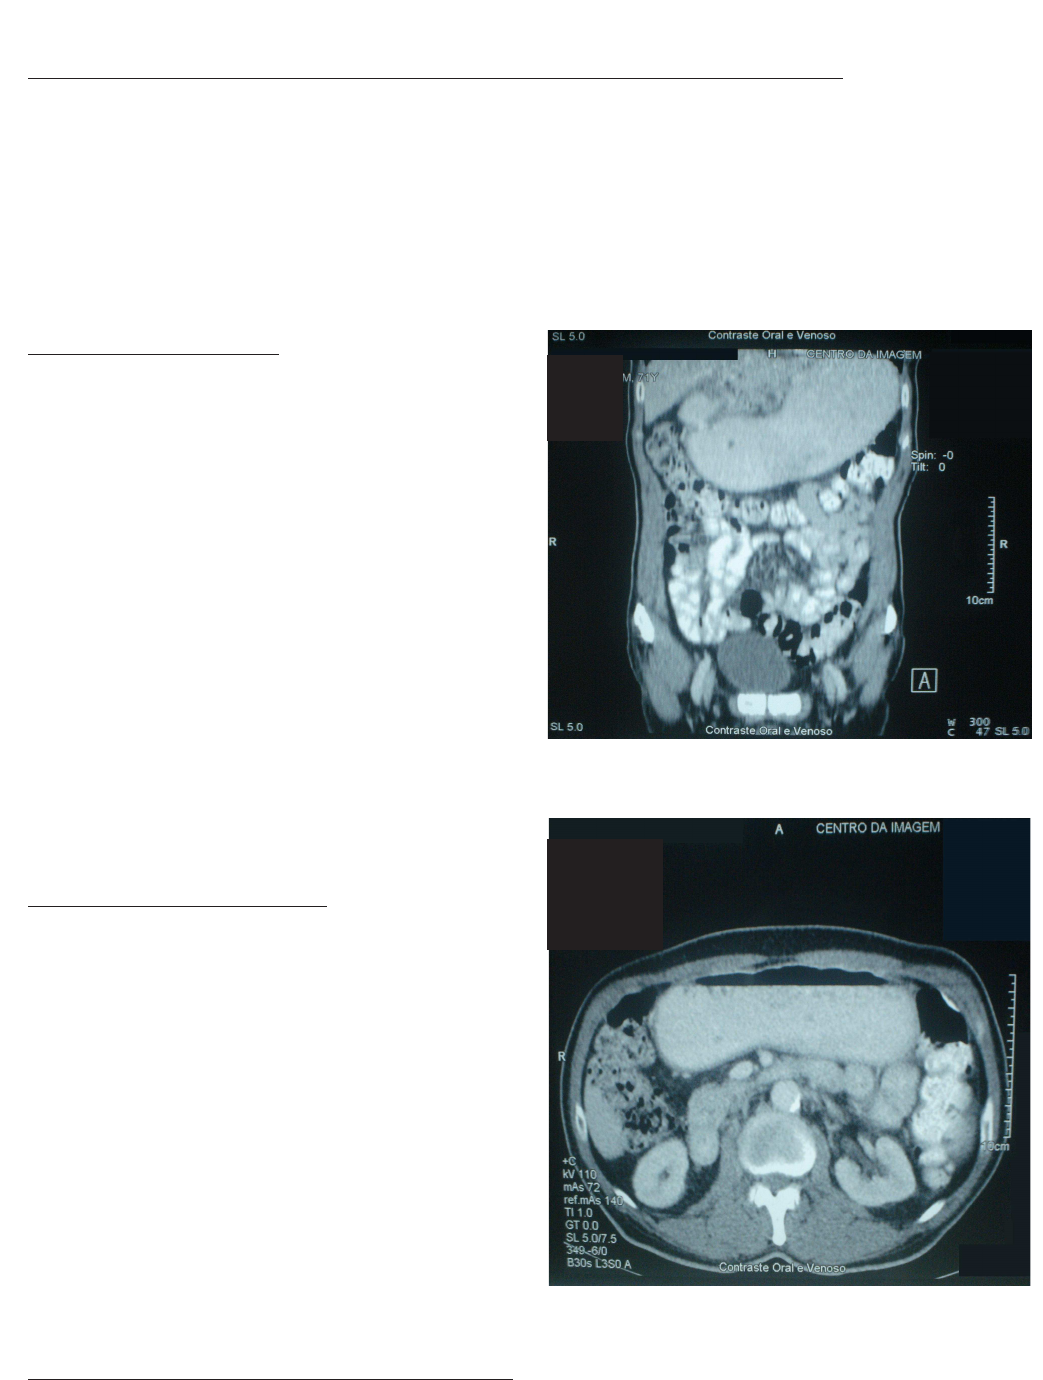

gástrico, não sendo feita biópsia. Foi solicitada uma

tomografia computadorizada (TC) abdominal, que eviden-

ciou o estômago dilatado, cheio de resíduos, esvaziamen-

to retardado, caracterizando um quadro obstrutivo (Figuras

1 e 2).

Figura 2 -Figura 2 -Figura 2 -Figura 2 -Figura 2 - TC abdominal – grande quantidade de resíduos no

estômago.

Figura 1 Figura 1 Figura 1 Figura 1 Figura 1 - TC abdominal – grande dilatação gástrica e estenose

pilórica.